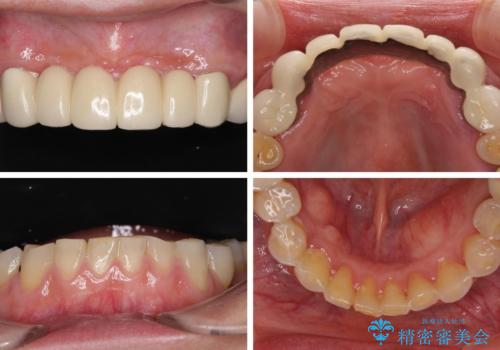

- 全顎的な歯肉からの出血と前歯の形態を気にして来院された患者様です。

診査の結果、上顎奥歯を中心に深い歯周ポケットが認められたため、歯周ポケット除去を目的とした歯周外科処置を行うこととしました。

また、前歯のブリッジへの咬合力の負担が大きく、土台となっている歯が揺れてしまっていたため、インプラント埋入により奥歯への負担を軽減することとしました。

歯周外科処置を行ったことで歯周ポケットはなくなり、毎回のブラッシングの度に嫌な思いをしていた出血は認められなくなりました。

上下前歯の見え方を気にされており、歯だけをみると大変長くなりましたが、笑ったときの口元は自然な外見となり、患者様には大変満足していただきました。